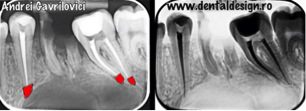

Intervenția chirurgicală a durat aproximativ două ore, a fost necesar un lambou trapezoidal prin care s-a dat la o parte gingia de pe os din dreptul caninului până în dreptul ultimului molar pe partea stângă. După aceea s-a extras restul radicular care a cauzat infecția, s-a frezat din osul vestibular și s-a îndepărtat formațiunea chistica. Concomitent s-a realizat rezecția dinților ale căror rădăcini au fost prinse în chist și s-a realizat adiția osoasă și repoziționarea gingiei cu ajutorul firelor de sutură.

*rezectia apicală: porțiunea din rădăcina colorată în roșu a trebuit îndepărtată deoarece era prinsă în procesul infecțios

Dacă se extrăgeau dinții de prima dată era nevoie doar de o procedură chirurgicală. Pentru rezolvarea situației actuale au fost necesare însă șase proceduri. De asemenea, defectul osos a fost mult mai mare acum decât ar fi fost atunci. Tratamentele de canal, rezecția dinților și granulele de os nu ar mai fi fost necesare dacă extracțiile s-ar fi realizat la timpul potrivit. Costurile au fost mult crescute din cauza agravării în timp a unei probleme minore. În final, cel mai important este ca pacientul să depășească acest obstacol apărut în calea zâmbetului sănătos și să înțeleagă că are pe cineva alături pe parcursul tuturor problemelor prin care trece.